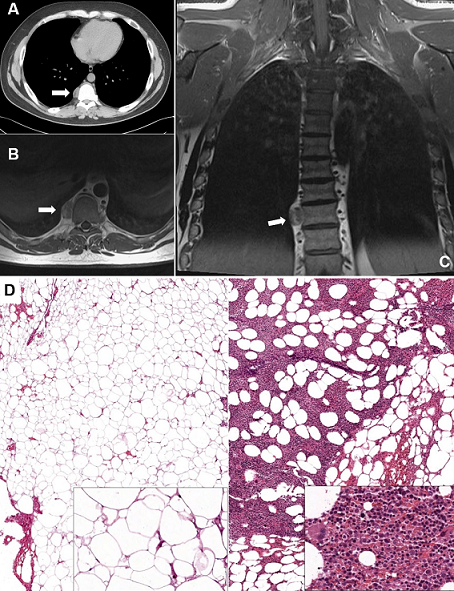

A 34-year-old male was admitted at our Department for back pain and a right paravertebral mass at the chest x-ray. His medical history was positive for beta-thalassemia major with normal routinely blood tests. A contrast-enhanced chest computed-tomography showed a 26 x 15 mm right solid paravertebral round-shaped lesion at T8-T9 levels, with a small inner component of adipose tissue (Panel A). Contrast-enhanced magnetic resonance-imaging showed irregular low signal intensity in long TR sequences, with mild enhancement after contrast administration (Panel B, Panel C). Surgical excision of the lesion by means of video-assisted thoracic surgery was scheduled for both definitive diagnosis and therapeutic purpose. Histopathologic examination revealed the presence of adipocytes mixed with mature hematopoietic cells (Panel D). Differential diagnosis included mediastinal myelolipoma (MM) and extramedullary hematopoiesis (EH). In fact, both of them are composed of fat and hematopoietic tissue. Mediterranean anemia is a common finding in patients with EH. However, the presence of a single capsulated tumor and the absence of abnormal hematopoietic cells led to a final diagnosis of MM. The patient is currently alive without recurrence 23 months after surgery. Myelolipoma is a benign tumor usually arising in adrenal glands. Less than 50 cases of MM have been described in the literature to date. Many Authors currently support the role of a triggering condition (both metabolic, infectious and neoplastic), which might be responsible for the growth of ectopic adrenal or hematopoietic tissue. Patient's history, radiologic, and pathologic features must all be taken into due consideration in differential diagnosis between MM and EH.